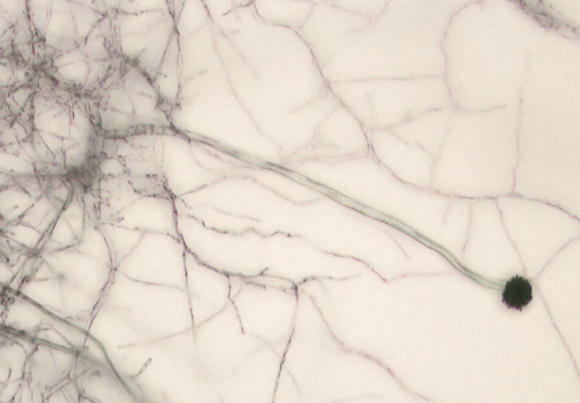

치명적인 폐 질환을 일으켜 매년 250만명의 사망자를 내는 것으로 알려진 곰팡이 ‘아스페르길루스 균류’가 지구 온난화로 분포 지역이 바뀌면서 북미, 유럽, 중국, 러시아 등 고위도 지역에서 더 확산할 수 있다는 주장이 나와 눈길을 끈다.

‘기후변화가 추동하는 아스페르길루스 종들의 지리적 이동과 그에 따른 식물과 인간 건강에 대한 함의’라는 제목이 달린 논문 초안은 이달 2일 공개됐다. 연구자들은 인간, 가축, 식물 등에 심각한 감염을 일으키는 아스페르길루스 속(屬)의 병원성 곰팡이 3개 종(種)의 지리적 분포가 기후변화 시나리오에 따라 어떻게 변할지 시뮬레이션했다.

특히 온대지방에 흔한 ‘아스페르길루스 푸미가투스’ 종은 2100년까지 분포 지역이 77.5% 증가해, 유럽 주민 900만명이 노출될 가능성이 있는 것으로 평가됐다. 사하라 이남 아프리카 등에서는 온난화로 아스페르길루스 곰팡이류가 살 수 없게 될 가능성이 있으나, 이 경우 토양 생태계 등에 영향이 있어 또 다른 문제가 생길 수도 있다.